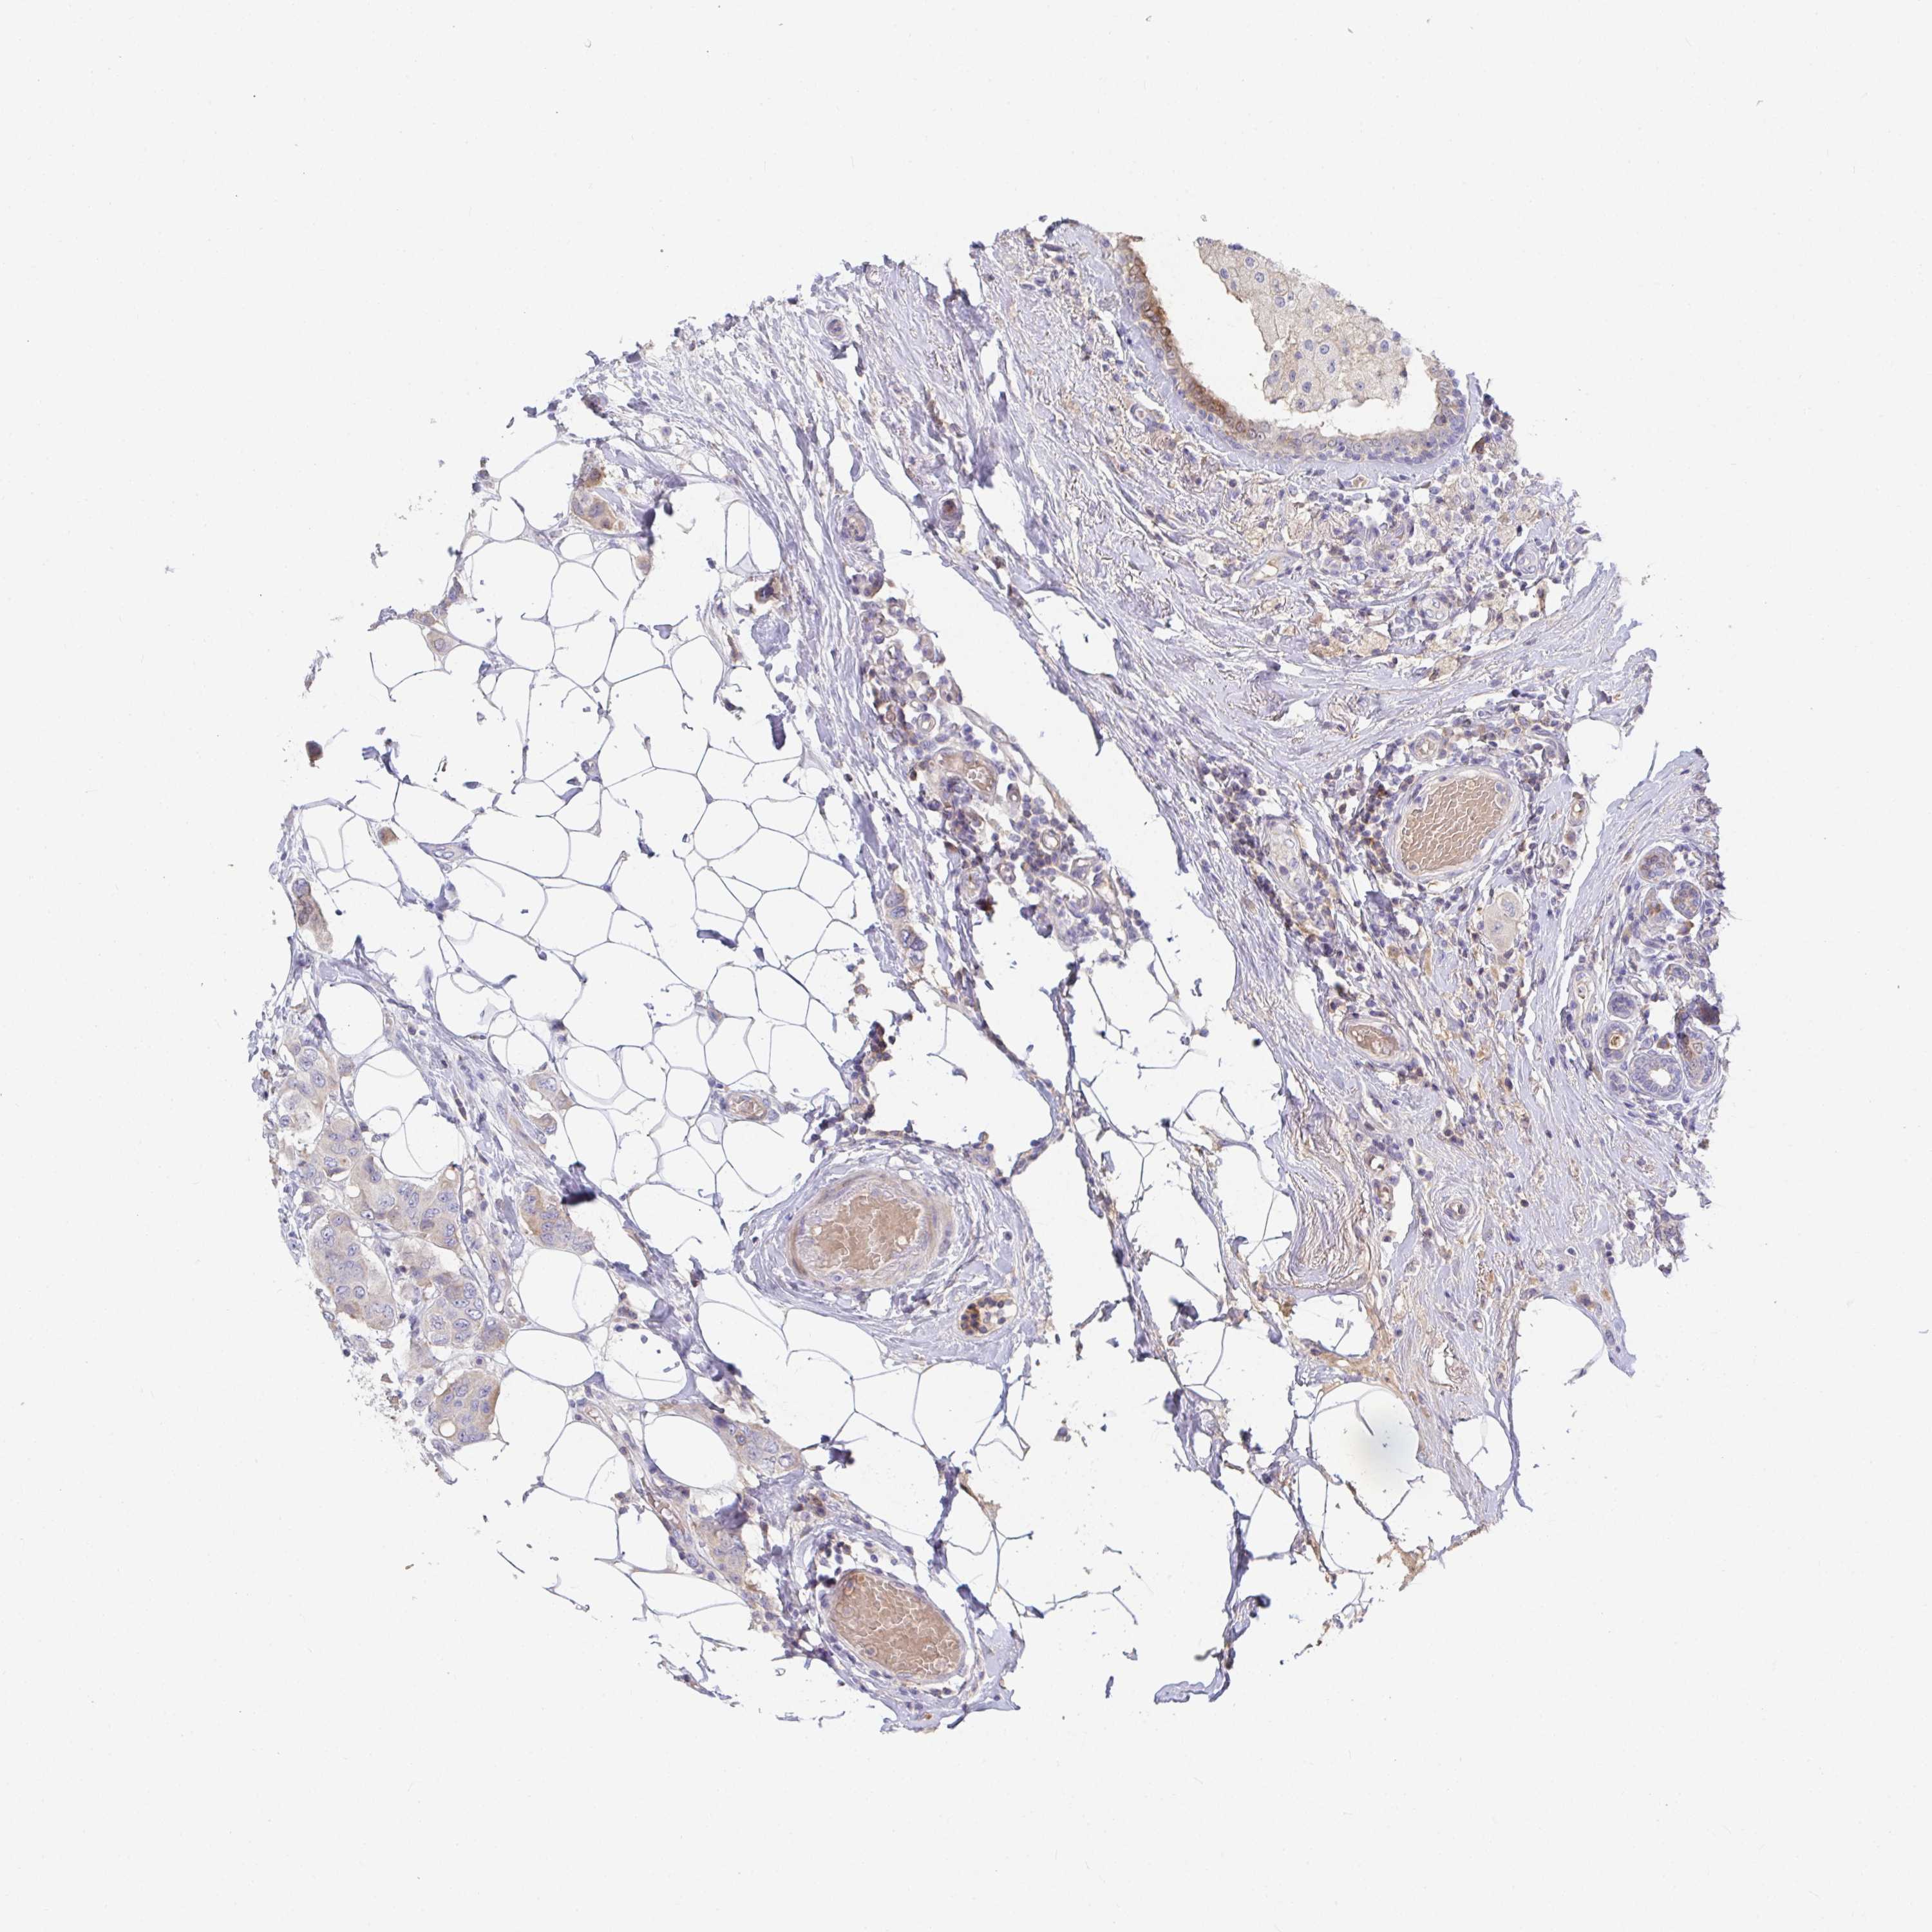

CANCER BREAST CANCER Show tissue menu

BRCA TCGA BRCA VALIDATION PROTEIN EXPRESSION